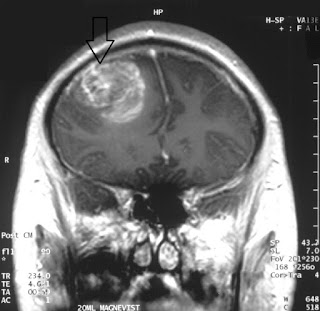

| MRI from a glioblastoma patient. Courtesy: Wikipedia |

similar fashion without going through the miniaturization process. Brain

cancer, for example, is one of the hardest tumors to treat, and every year,

about 10,000 patients are diagnosed with glioblastoma (GBM), the most common

primary brain cancer. In a recent paper, Juli Bagó and her